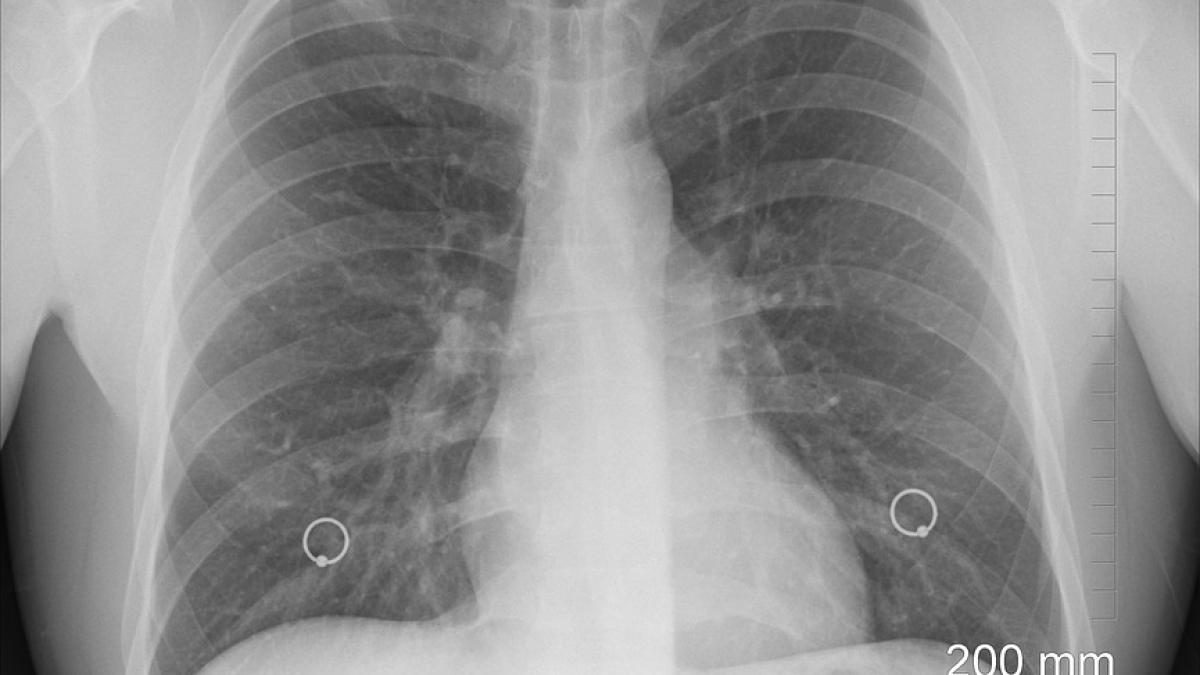

mituri-cancer-pulmonar_80386300 Mituri medicale despre cancerul pulmonar / Foto: Pixabay

În articol găsești mai multe mituri medicale despre cancerul pulmonar.